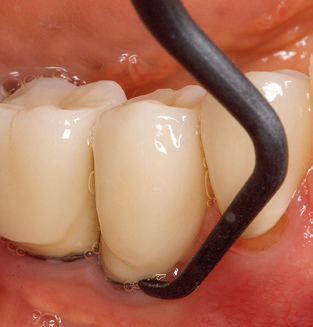

Good illumination of the working field facilitates the process considerably. The system used by the authors achieves this thanks to a 5x LED ring integrated in the handpiece. Naturally, a range of working tips for different indications is also offered. A straight, universally employable tip is the basic instrument required for machine cleaning of natural teeth (Fig. 5a and b). Curved tips, which allow access to exposed furcations, are also available for hard-to-reach areas in the posterior region (Fig. 6).

Fig. 4: Flexible probes with millimetre markings are recommended for the probing of dental implants (e.g. Colorvue Kit PCV11KIT6, Hu­Friedy). – Fig. 5a and b: A straight working tip (1P, W&H Dentalwerk Bürmoos GmbH) is a suitable instrument for use on all natural teeth. – Fig. 6: Curved working tips (3Pr/3Pl, W&H Dentalwerk Bürmoos GmbH) lend themselves to the processing of difficult-to-reach areas of the tooth and root surfaces (e.g. furcations). – Fig. 7: The tapered, hexagonal implant cleaning tip (1I, W&H Dentalwerk Bürmoos GmbH) permits atraumatic and efficient cleaning of the crown and abutment surfaces. – Fig. 8: Titanium and carbon curettes are suitable instruments for the manual cleaning of the implant surfaces.